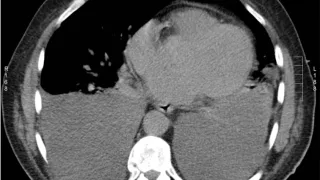

午前の病院での仕事今朝は快晴,最低気温2℃, しかし最高は15℃予報.春の気配とともに, スキーシーズンの終わりも見えてきました.8時前に病棟へ. 敗血症性ショックで治療していた患者さんは血圧が安定.昇圧薬ノルアドレナリンの中止を指示しまし...